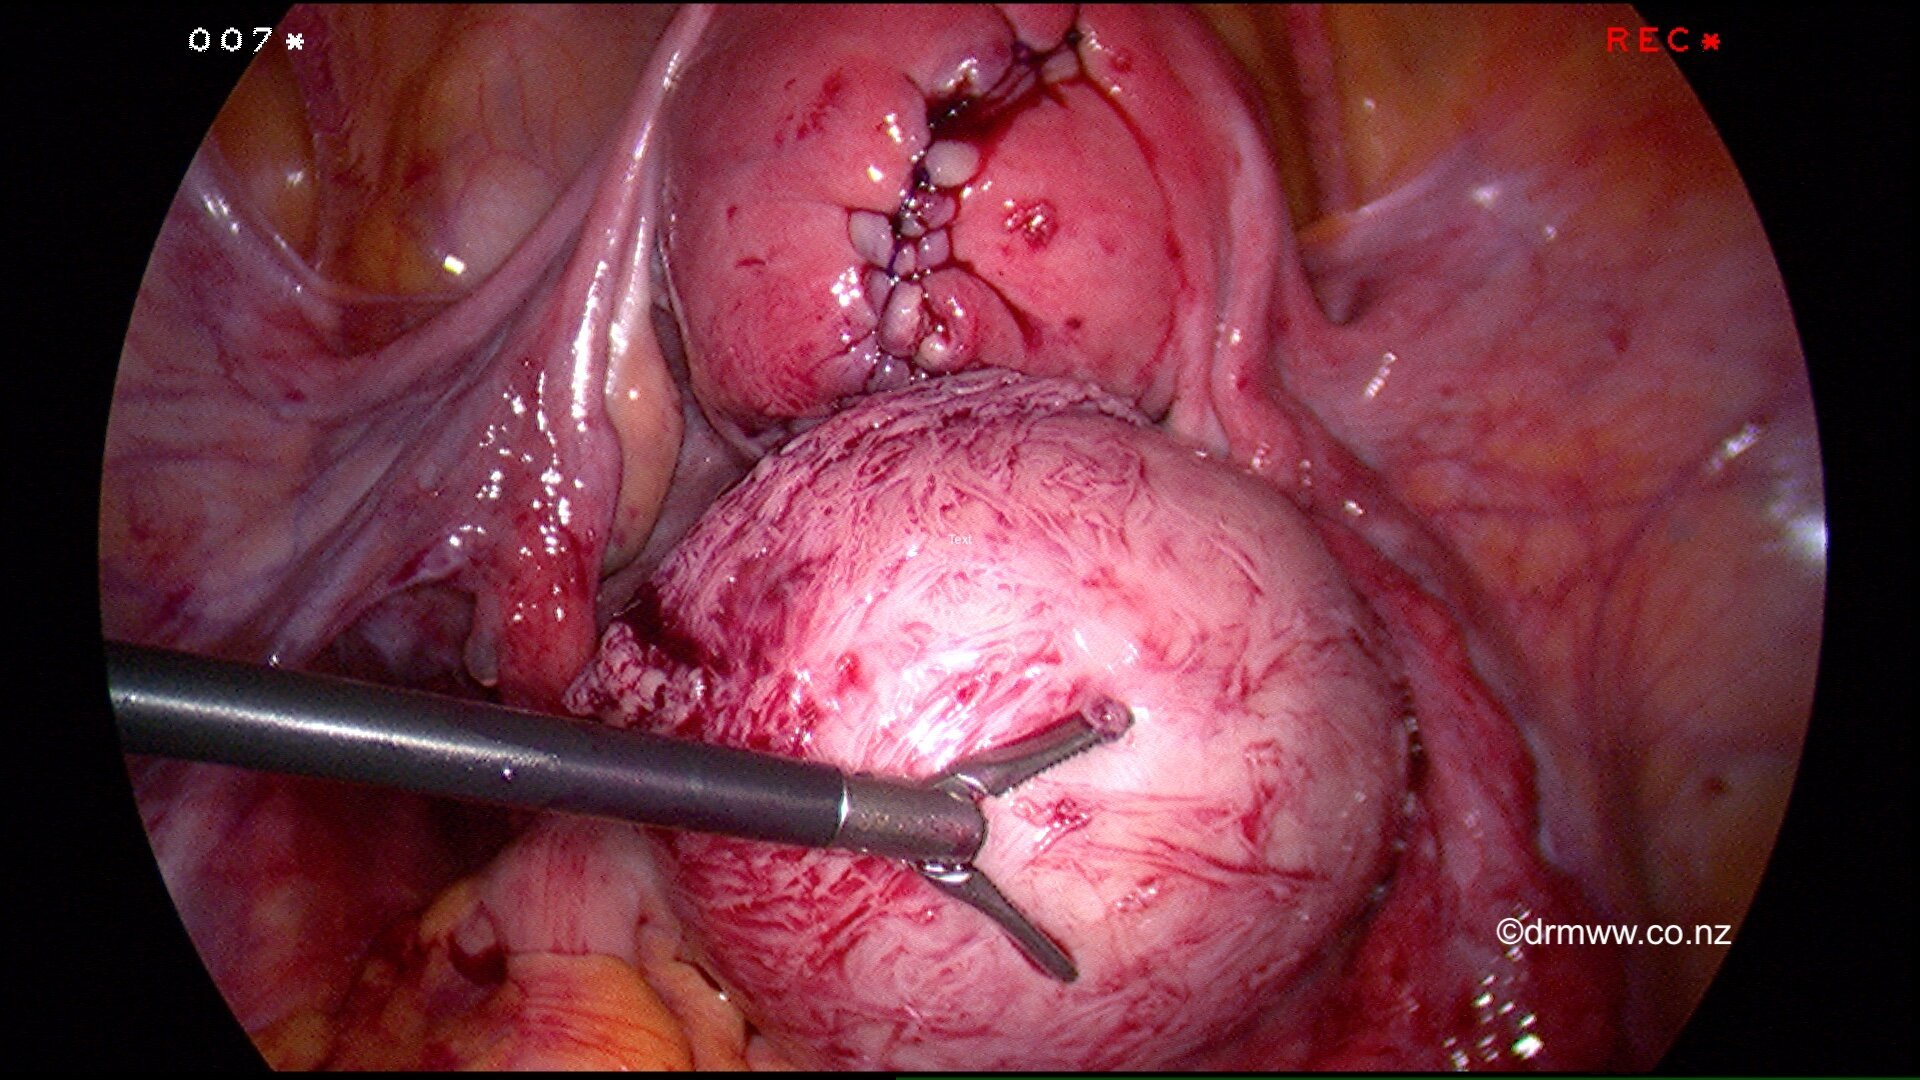

Dr Wynn-Williams has a particular interest and skill in the surgical management of fibroids. For young women, those that wish to preserve their fertility or difficulty conceiving due to fibroids, then myomectomy performed either Hysteroscopic Myomectomy (Link to Operative Hysteroscopy page) or by Laparoscopy (keyhole) Myomectomy (link to Lap Myomectomy Page) can be very effective management options. Occasionally the surgery cannot be performed through keyhole surgery and is achieved through an open procedure. In the case of women having a laparoscopic or open myomectomy, they must avoid conceiving for six months. They should have a Caesarean Section for delivery to prevent the rare risk of rupture of the uterine scar in labour.

A repaired uterus and the fibroid that was removed laparoscopically.